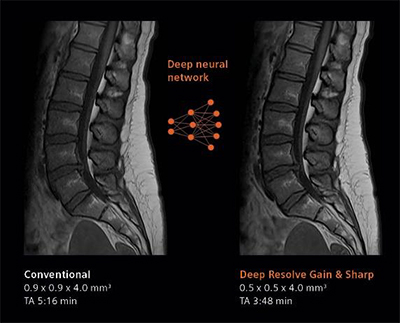

デジタル化により高画質と撮像時間の短縮を実現するべく,画像再構成にAI技術を用いて開発されたのがDeep Resolve(ディープ・レゾルブ)。

Deep Resolveは,ディープラーニング(深層学習)とターゲットデノイジング(ノイズの標的除去)により画像のノイズ除去や撮像した画像を高分解能化することで,高品質な画像の取得と撮影時間の短縮*1を可能にする。検査精度やワークフローの向上のほか,被検者の快適性や質の高い医療へのアクセス向上が期待される。

左:ルーチン検査画像, 右:Deep Resolveによる再構成画像